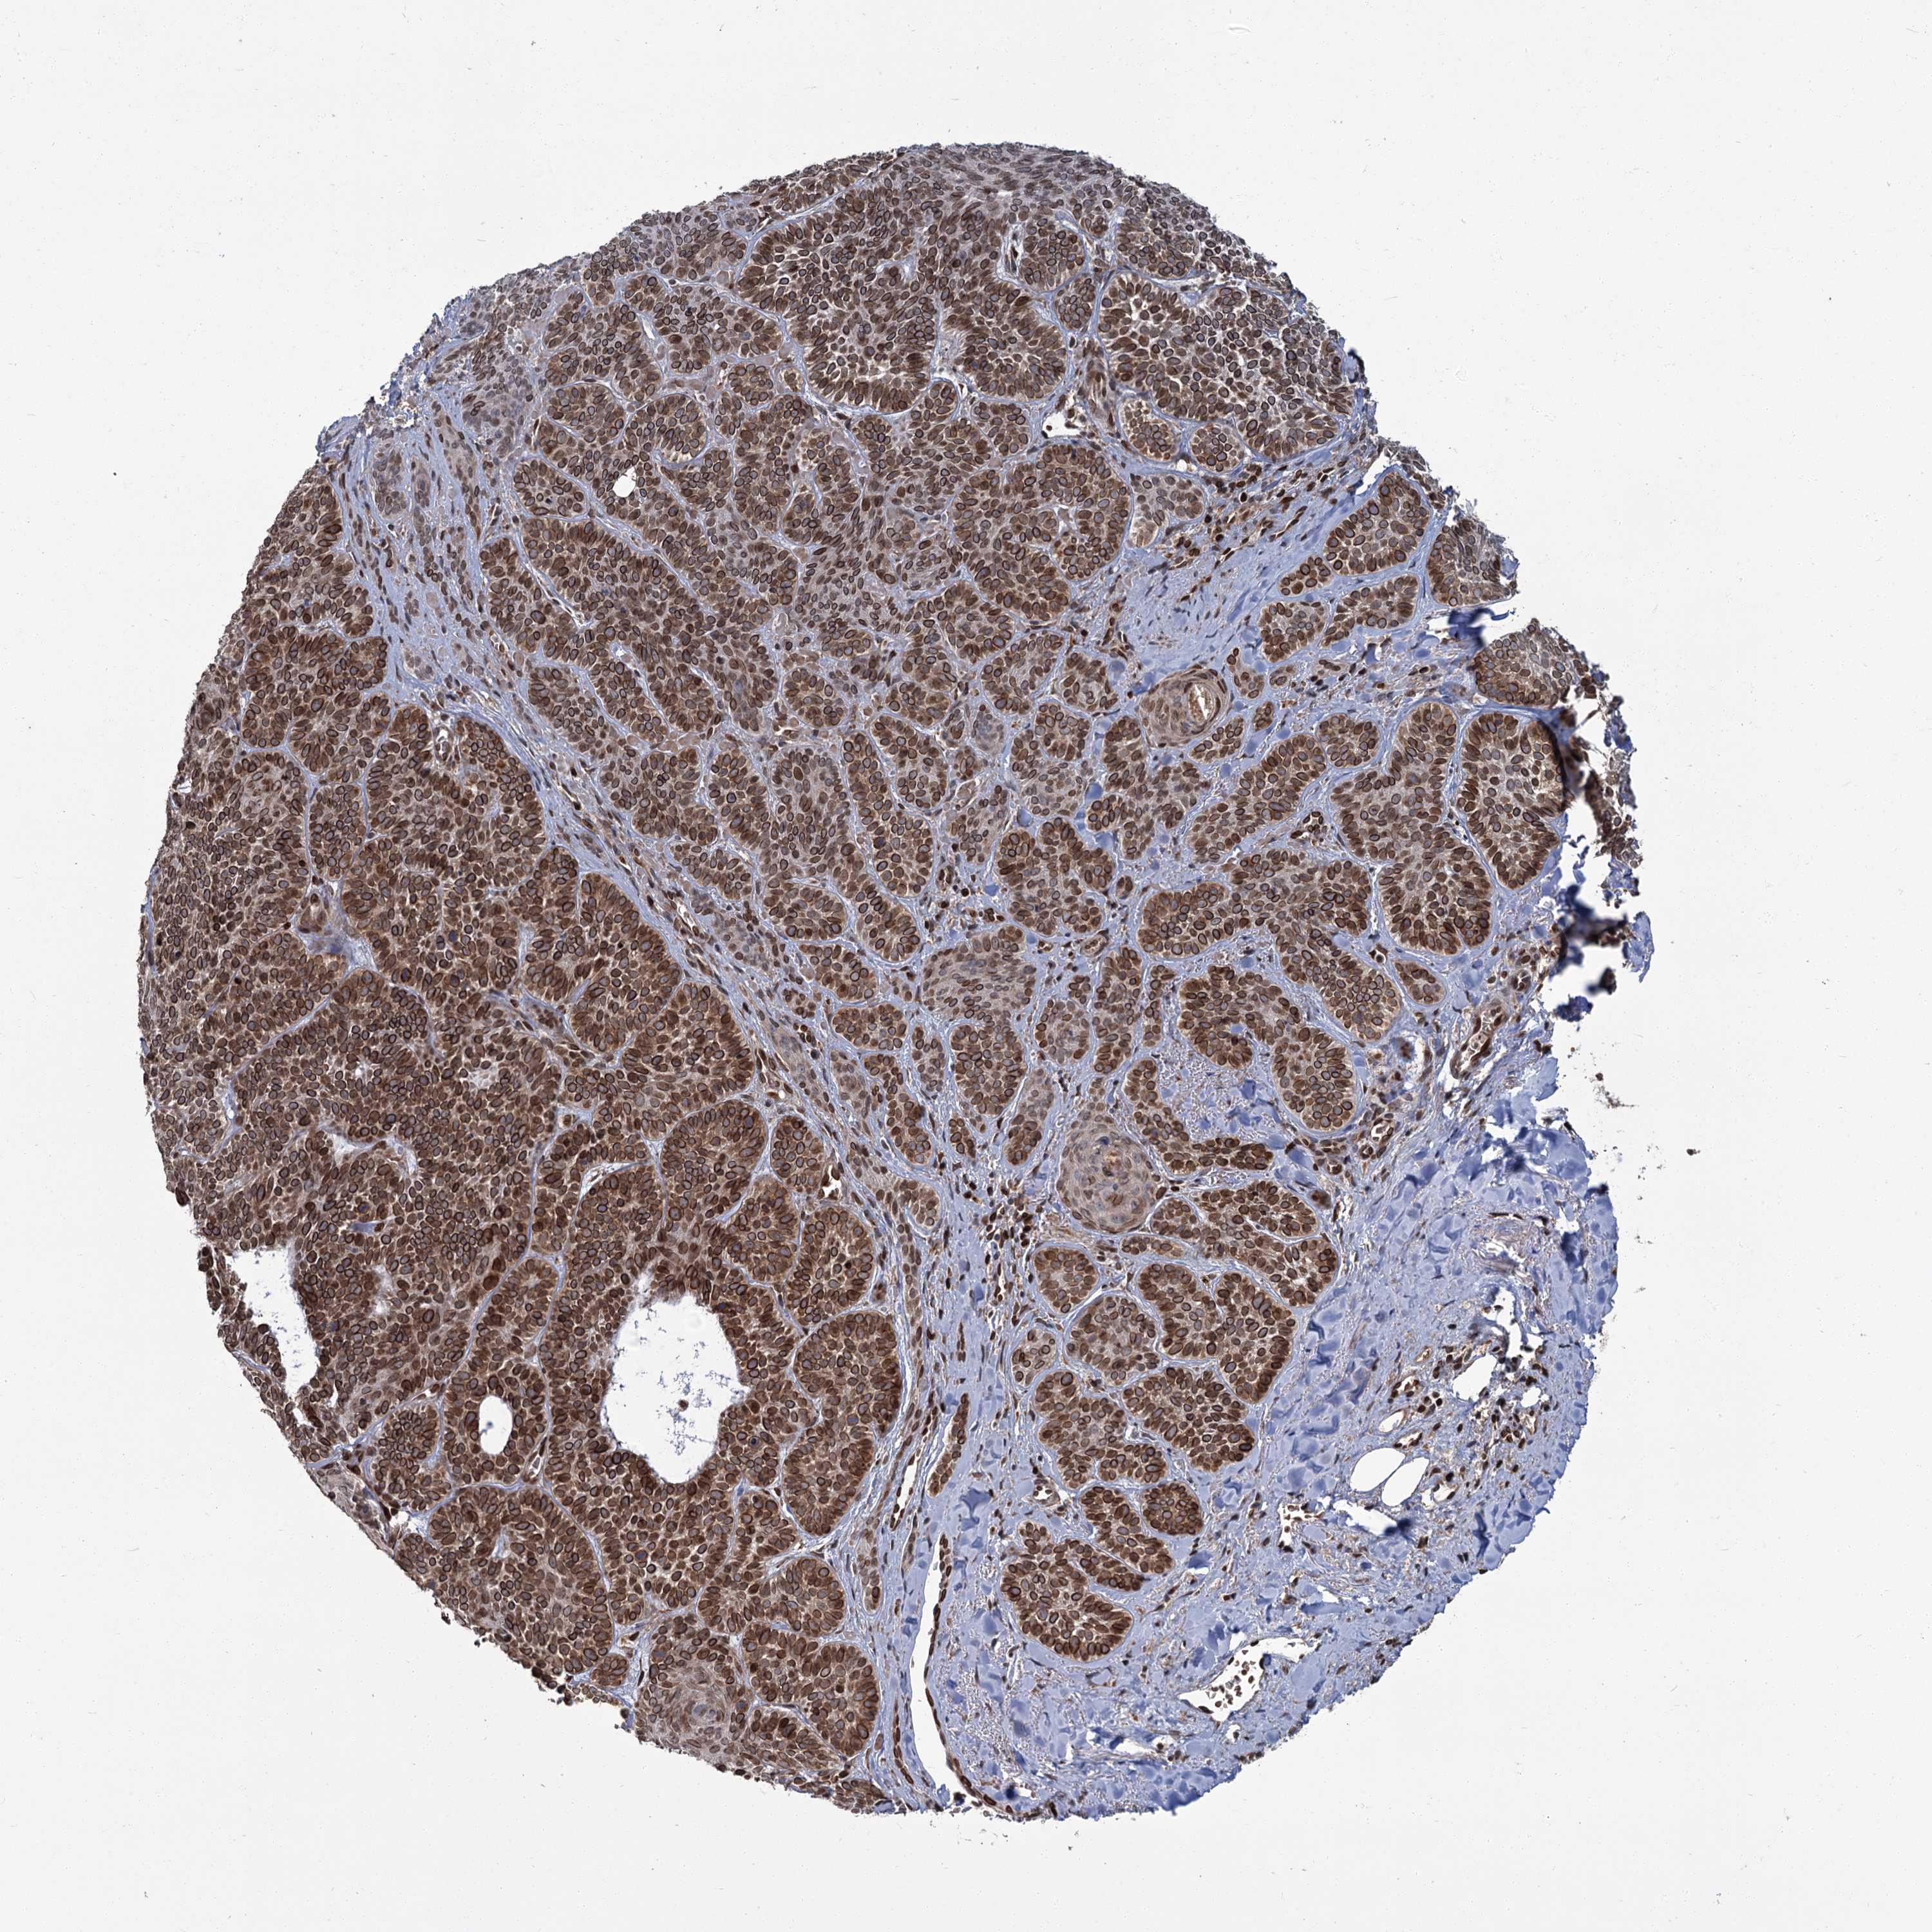

SKIN CANCER - Protein expressioni

A mouse-over function shows sample information and annotation data. Click on an image to view it in a full screen mode. Samples can be filtered based on level of antibody staining by selecting one or several of the following categories: high, medium, low and not detected. The assay and annotation is described here.

Antibody stainingi

Antibody staining in the annotated cell types in the current human tissue is reported as not detected, low, medium, or high, based on conventional immunohistochemistry profiling in selected tissues. This score is based on the combination of the staining intensity and fraction of stained cells.

Each image is clickable and will lead to virtual microscopy that enables deeper exploration of all samples and also displays staining intensity scores, fraction scores and subcellular localization as well as patient and tissue information for each sample.

Antibody HPA037786

Antibody HPA038034

Antibody HPA038867

Antibody HPA038868

High

Strong

>75%

Nuclear

Squamous cell carcinoma, metastatic, NOS